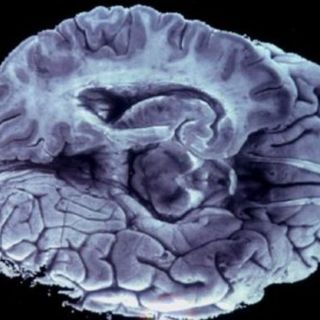

AlzTools se utiliza para analizar los datos tomados por un escáner cerebral, en vez de un satélite de observación de la Tierra. Analizan zonas del cerebro como el hipocampo, cuya atrofia está relacionada con el Alzheimer.

“Esta técnica nos permite cuantificar una atrofia del lóbulo temporal. Si sabes dónde mirar, puedes estimar cuánto volumen se ha perdido”, expresó.

Según ESA, la herramienta es totalmente revolucionaria, pues hasta ahora los doctores estudiaban las imágenes cerebrales “a simple vista”, actualmente es posible desarrollar un método más sencillo y fiable para diagnosticar el Alzheimer.